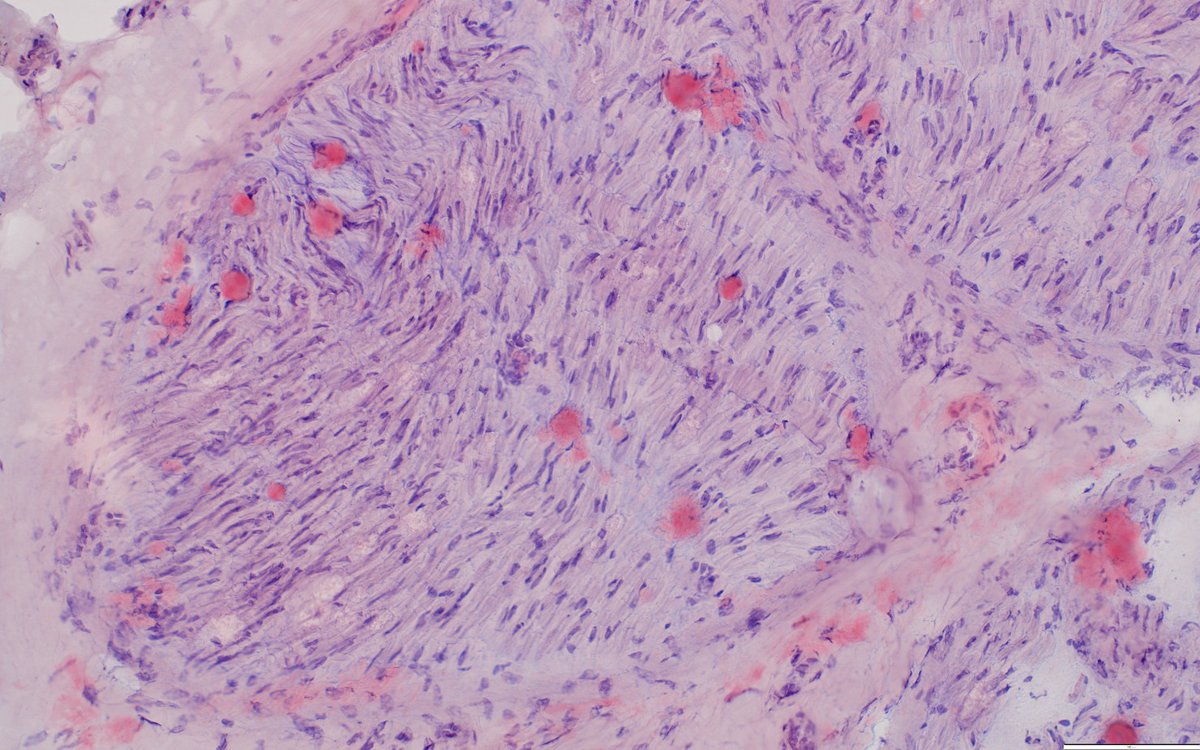

The Phase III CARES trial of #anselamimab in #ALAmyloidosis did not meet its primary endpoint, but showed clinically meaningful benefit in a predefined high-risk subgroup. More details to follow at upcoming meetings. @BU_Amyloidosis astrazeneca.com/media-centre/p…